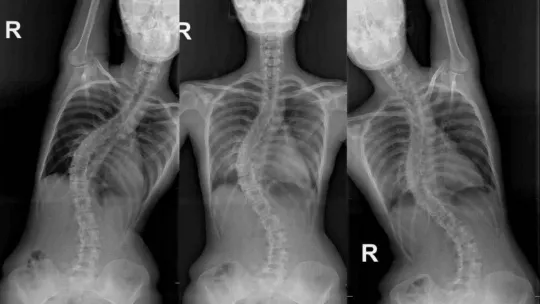

Rusya’da yaşayan 22 yaşındaki Modelina Aleksandra, 12 yıl önce omurgasında eğrilik olduğunu fark etti. Ailesi ve yakınları tarafından birçok ülkeye tedavi için götürülen Aleksandra en sonunda Türkiye’nin yolunu tuttu. Her geçen gün omurgasındaki eğriliğin arttığını fark eden Aleksandra, yaptığı araştırmalar sonucu Bursa’ya geldi. Skolyoz eğriliğinin 60 derece olduğu tespit edilen Aleksandra, Robotik Skolyoz Cerrahisi ile sonunda sağlığına kavuştu.

Aleksandra’nın kendilerine skolyoz şikâyetiyle geldiğini belirten Opr. Dr. Yunus Uysal, “Rusya’dan bize filmlerini gönderdiğinde omurgasında yaklaşık 60 derecelik bir eğriliği vardı. Ameliyat olması gerektiğini ilettik. Bizim önerimiz doğrultusundan Rusya’dan Türkiye’ye geldi. Burayı tercih etmesinin sebebi, Türkiye’deki tıp uygulamalarının üst seviyede olması olmuş. Kurumumuzda mevcut olan robotik omurga cerrahisini tekniğinden faydalanarak skolyoz ameliyatını gerçekleştirdik. Ameliyattan önce 60 derece olan eğriliği, neredeyse ’0’ derecesine kadar düzelttik ve yüz güldürücü bir sonuç aldık” diye konuştu.